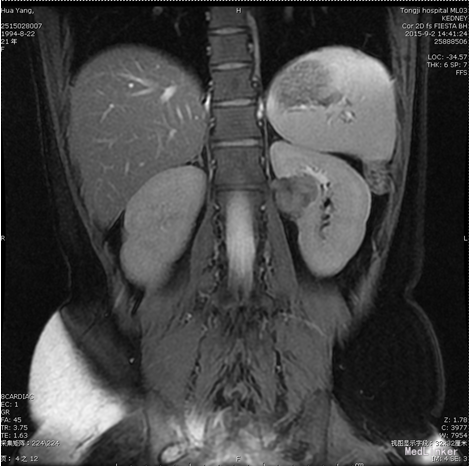

患者,女,21岁。 主诉:体检发现左肾占位4月余。 现病史:患者于患者约4月前单位行体检时发现左肾占位,在外曾于当地医院行CT检查提示“左肾良性肿块,不排除肾嗜酸细胞瘤可能”。

查体:T36.6℃,P84bpm,Bp104/66mmHg,双肾区叩痛阴性,外生殖器无畸形,双下肢无水肿。 辅助检查: 2015.9.15浠水县人民医院CT检查提示“左肾良性肿块,不排除肾嗜酸细胞瘤可能”。 2015.9.3我院MRI示“左肾占位,多考虑肿瘤性病变”。 双肾ECT检查示:双肾血流灌注、摄取功能大致正常,排泄通。

诊断:左肾肿瘤 处理:后腹腔镜下左肾部分切除术。以免疫治疗应用重组人白介素-2预防肿瘤的复发。